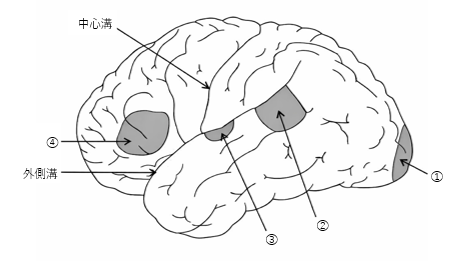

大脳皮質の機能局在を模式図に示す。ブローカ野(運動性言語中枢)はどれか。1つ選べ。

a. ①

b. ②

c. ③

d. ④

解答を見る

d